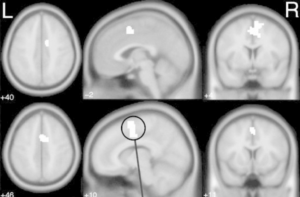

Medial prefrontal cortex activation in OCD-diagnosed patients (Kaufmann et al., 2013)

By strengthening this area of the frontal cortex, we’ve seen (both in the research and in our clinical practice) remarkable improvements in OCD symptoms like checking behaviors, rituals, and more (all of which are downstream of atypical threat detection).